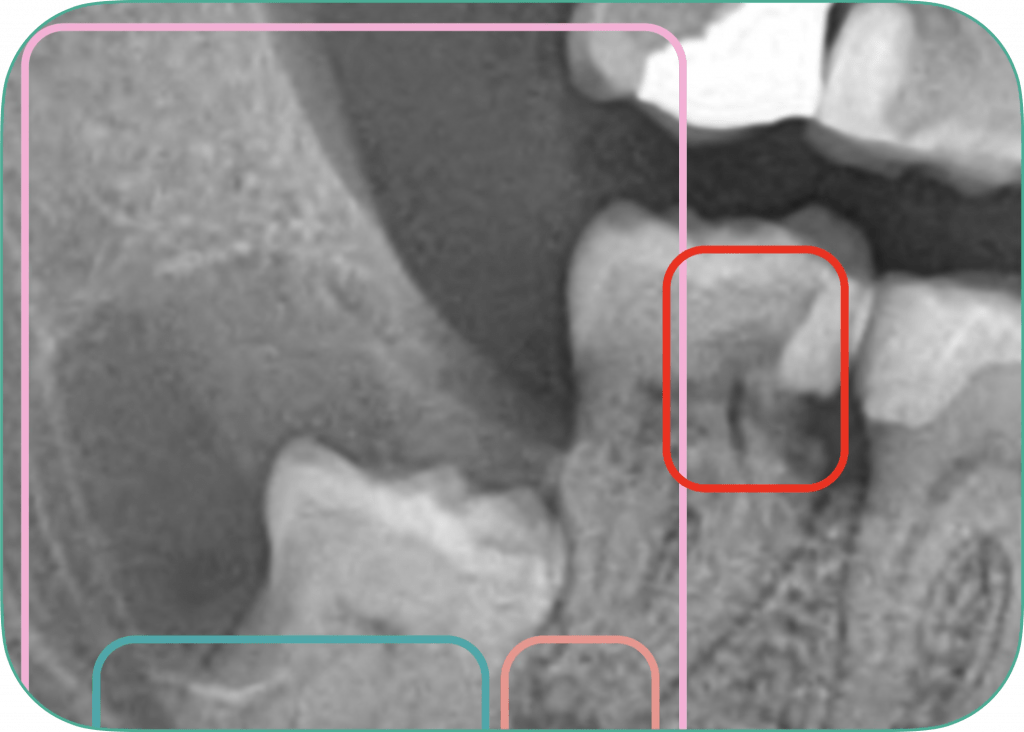

2) Wykrywanie problemów klinicznych

Potencjalne obszary problemowe są wyróżnione, ale nie zasłaniają obrazu, aby nie zakłócać oceny lekarza.

3) Analiza obszarów i wybór, co pokazać pacjentowi

Wybrane obszary oznaczone są kolorami ułatwiającymi analizę i zrozumienie wagi problemu przez pacjenta.